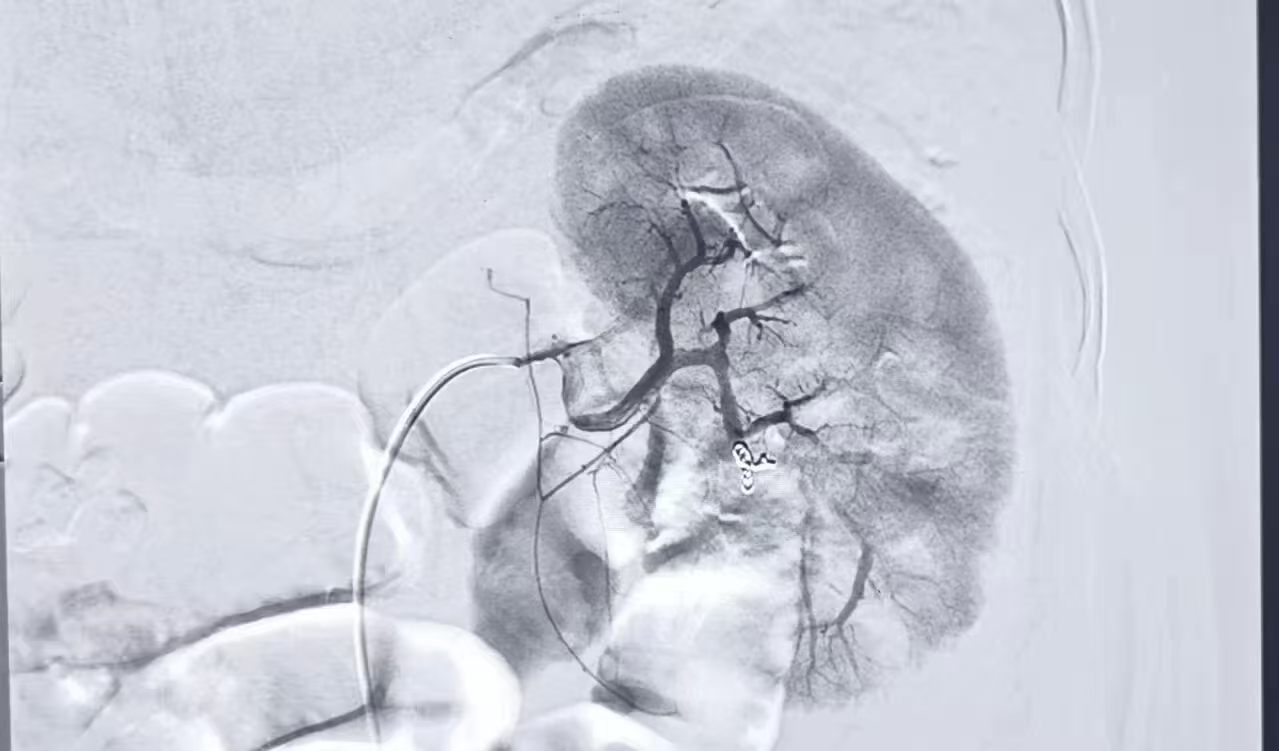

时间就是生命,速度决定生机。考虑到患者病情危重,传统开放手术风险极高,介入科团队果断制定微创救治方案——不开腹,通过血管造影定位出血点,采用栓塞材料封堵,最大程度保住肾脏。在导管室,专家们凭借精湛技术,经股动脉一个针眼大小的穿刺点,将导管精准送至目标肾动脉,造影明确出血点后,立即注入专用栓塞材料,成功封堵了破裂血管。整个肾动脉造影和栓塞术仅耗时约30分钟,患者出血当即得到有效控制。这项微创介入技术,以最小创伤、最快速度为受损肾脏打上精准“生命补丁”,避免了肾切除的悲剧,为后续治疗筑牢坚实基础。

造影后